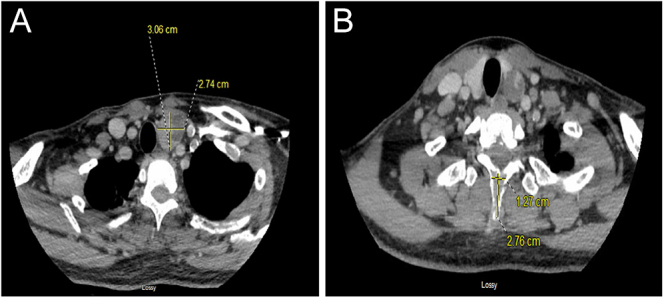

Summary: Primary hyperparathyroidism (PHPT) is a disorder in which excessive parathyroid hormone (PTH) is secreted from the parathyroid glands. The cause of PHPT is most commonly parathyroid lesions such as parathyroid adenoma. The clinical manifestations of PHPT include hypercalcemia, nephrolithiasis, bone disease and rarely pathological fractures and brown tumors, which arise within the foci of osteitis fibrosa. Brown tumors are benign intraosseous tumors that occur because of excessive osteoclast activity. Because of advances in medical care, early diagnosis and treatment have meant that diagnosing PHPT in the setting of multiple brown tumors is particularly rare. Here, we present a case of a young man with prolonged PHPT from a giant parathyroid adenoma with multiple brown tumors causing pathological fractures. Definitive treatment of PHPT is parathyroidectomy with particular attention to the risks for hungry bone syndrome (HBS) postoperatively.

Learning points: Pathological fractures from brown tumors are a rare but significant concern in prolonged PHPT, and a multidisciplinary approach is required including orthopedic surgery, otolaryngology and endocrinology.It is important to assess PTH and calcium in the context of hypercalcemia with bone lesions to avoid potential diagnostic delays.Postoperative parathyroidectomy patients with large parathyroid adenomas, elevated alkaline phosphatase, elevated PTH and the presence of brown tumors are at particularly high risk for HBS.Very high levels of PTH, calcium, alkaline phosphatase and multiple brown tumors should raise concern for a potential case of parathyroid carcinoma.Indications for genetic testing for inheritable parathyroid disease include patients younger than 30 years old, those with multigland disease, those with a family history of hypercalcemia or syndromic disease and those with atypical parathyroid adenoma and parathyroid carcinoma.